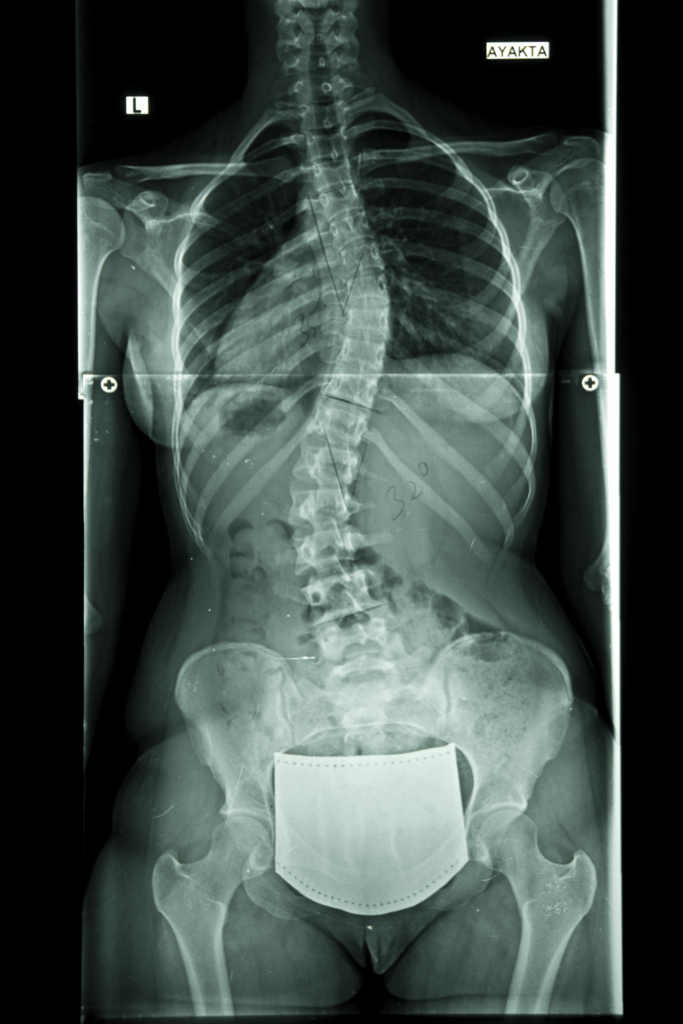

- ma stwierdzoną skoliozę,

Nie musisz mieć badań, na pierwszej wizycie po zbadaniu dziecka ustalimy czy w przypadku Twojego dziecka takie badania są potrzebne. Jeśli posiadacie badania RTG kręgosłupa to przygotuj je na pierwszą wizytę